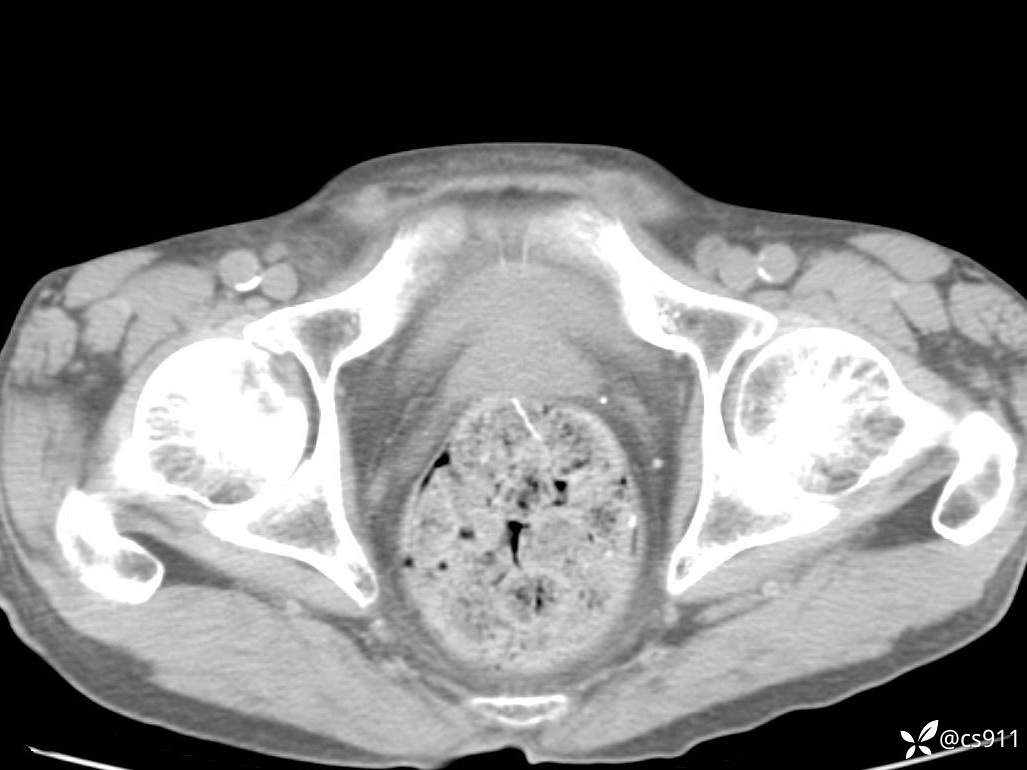

急腹症之急诊CT,原因?答案公布

男,77岁,腹痛、腹胀伴恶心呕吐1天。呕吐胃内容物,非喷射性呕吐,有咖啡色样胃内容物,诉有胃穿孔病史。查体:全腹平,下腹部压痛,全腹无反跳痛,叩诊呈浊音,移动性浊音阴性,肠鸣音减弱,1-2次/分。肛检:直肠未扪及明显肿物,可触及大量粪块。

T 36.6℃ P 80次/分 R 26次/分 BP 100/60mmHg

白细胞(WBC) H 14.55 10e9/L 4-10

红细胞(RBC) 4.58 10e12/L 4.3-5.8

中性粒细胞百分率(NEUT%) H 85.7 % 40-75

血淀粉酶(AMY) HH 1859 U/L 35-135

癌胚抗原(CEA) H 27.44 ng/ml 0-5

呕吐物 潜血试验 * 阳性 阴性

患者轮椅入室检查神志清楚, 能配合摆位和呼吸